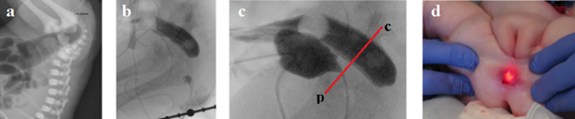

Figure 2 Figures and description from article by Chowdhury et al.8 In 17‐year‐old girl meconium passed within 24 h of life.   She developed features of constipation after weaning at about 6 months of age.  Gradually the constipation worsened. She did not pass stool for the last 9 days at the time of referral. Barium enema showed a dilated colon, and the lower end of the rectum was located high up with a beak‐like appearance (Figure 1a). Digital rectal examination   under anesthesia revealed a thick diaphragm, about 3 cm from anal verge with a central hole, through which hard fecal matter was visible (Figure 1b&c).  The thick membrane was excised circumferentially using monopolar coagulating diathermy from anal approach.

The sigmoid and descending colon are dilated, but the sigmoid colon is located in the small pelvis, that is, it is not elongated, which does not correspond to the severe chronic constipation described in the article. Second, the white arrow in Figure 1a shows the normal connection between the rectum and the closed anal canal. This means that the stenosis is located lower, i.e. in the anal canal. Thirdly, the diagrams do not correspond to the anatomical location of the organs. However, the membrane is located significantly below the pubococcygeal line we drew (red line). This line corresponds to the location of the puborectalis muscle, which is located between the rectum and the anal canal. From which it follows that the membrane is in the anal canal. Fourthly, the possibility of excision of the membrane from the anal access also indicates its location in the anal canal. Thus, the case described by the authors confirms our observation that the so-called rectal stenosis is in the anal canal, i.e., it is anal canal stenosis (ACS). Secondly, stenosis is a membrane with a hole in the center, which is also confirmed by a group study on the classification of anorectal anomalies in Japan.9

Diagnosis in newborns with complete obstruction involves inserting a rigid catheter through the normally formed anus until it stops. In AAC, the catheter stops about 1 cm from the anal verge. 30 hours after birth, during fluoroscopy, a radiograph of the anorectum is taken in the lateral projection, at that moment when, during compression of the abdomen between the doctor’s palms, gas from the rectum penetrates the anal canal. The location of the membrane is determined between the gas that has penetrated the anal canal and the probe inserted through the anus. The reflex of the anal canal opening in ARM without a functioning fistula is shown in Figure 4.

Figure 4 X-ray examination of a newborn with ARM without a visible fistula. (a). At rest, the gas was in the rectum at the level of the pubococcygeal line (p-c). (b). When the rectal pressure increased to a certain level, the anal canal opened, and the gas approached the skin of the perineum.